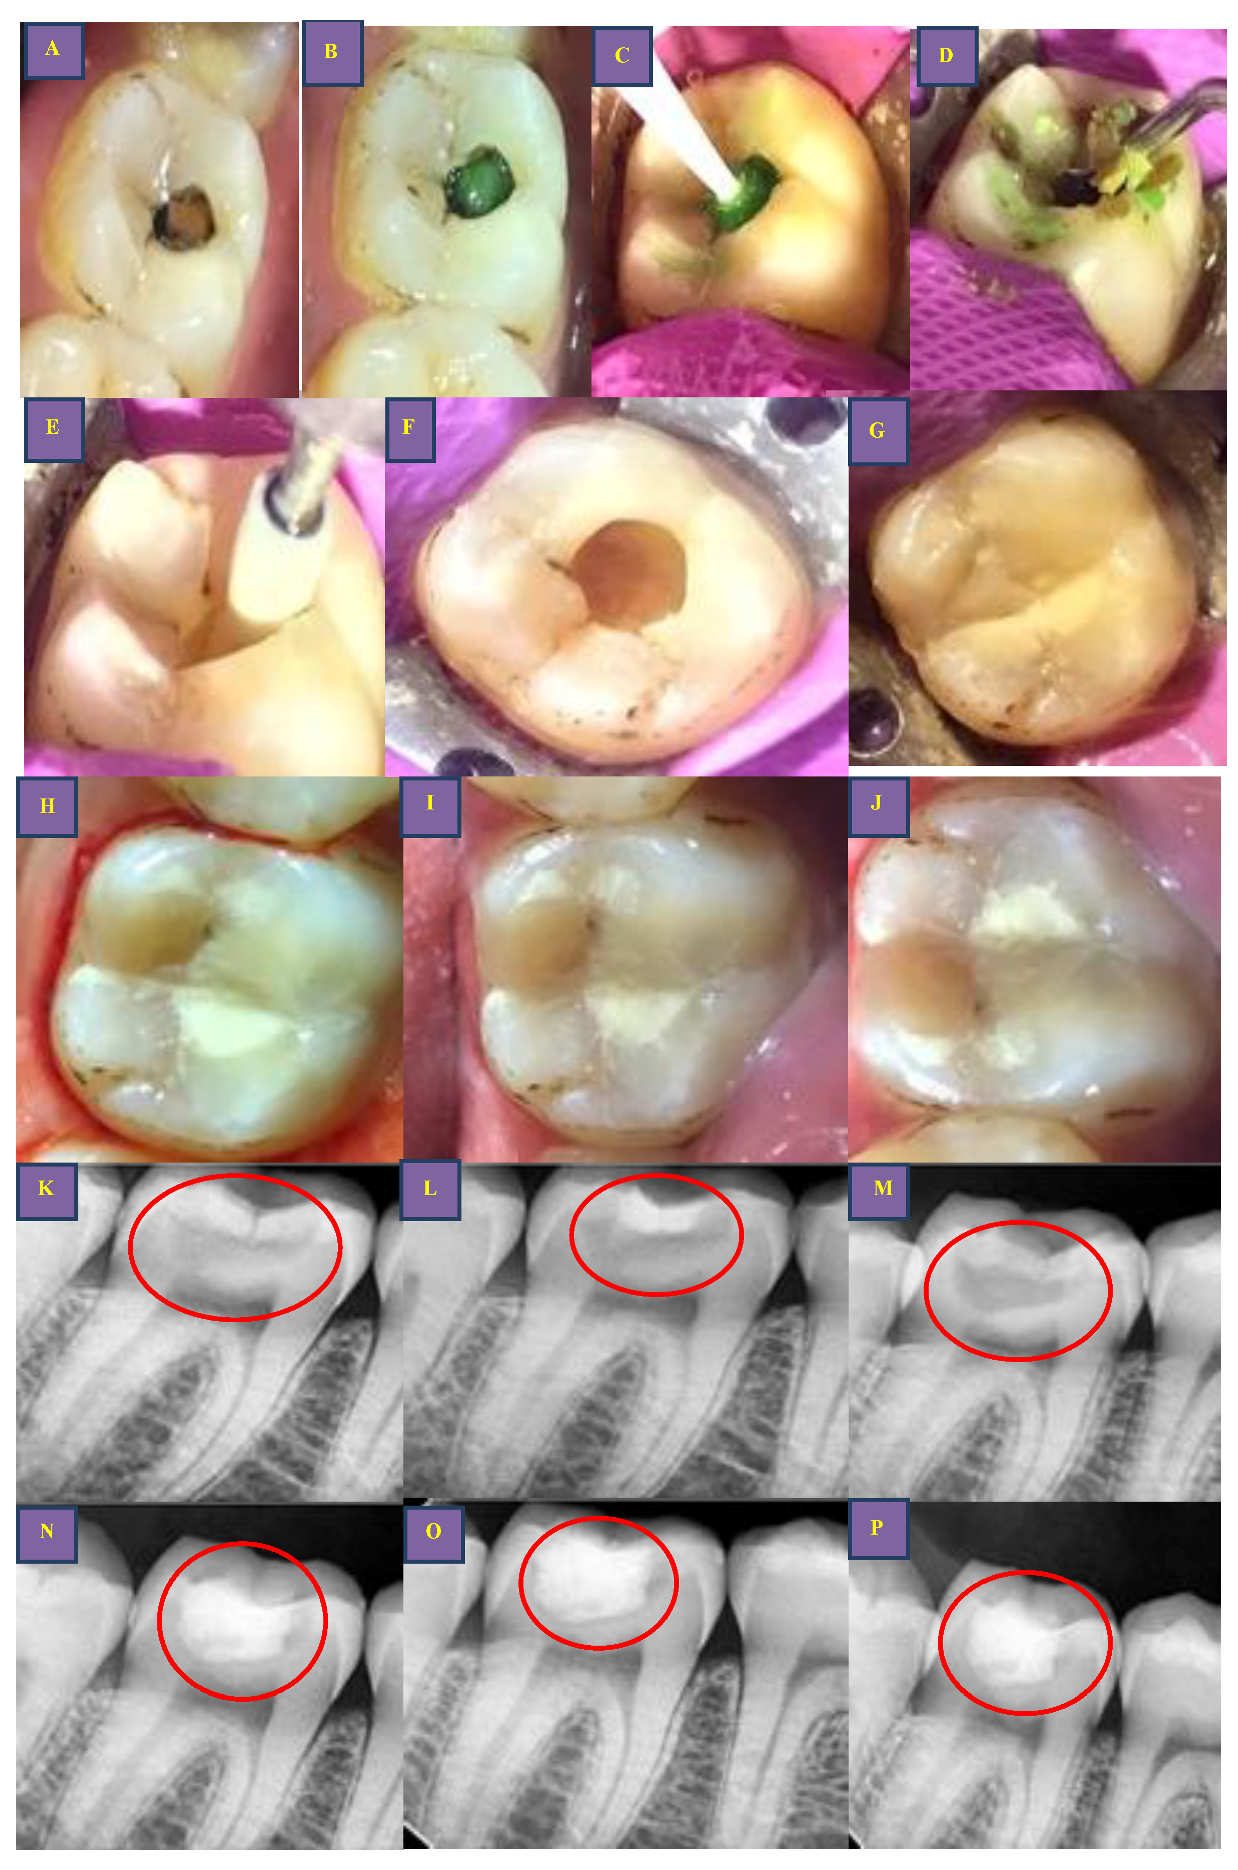

2.4. Treatment

Caries Excavation and Treatment Time